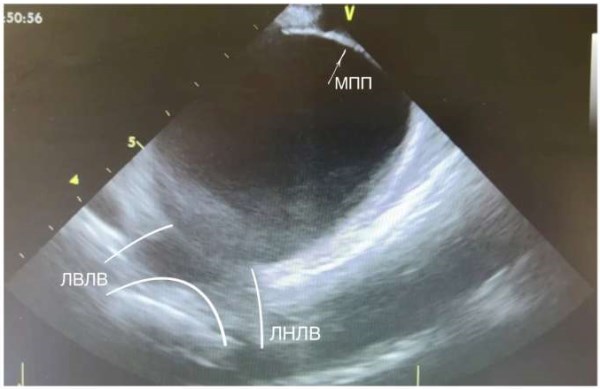

Рис. 6. Межпредсердная перегородка (указана белой стрелкой), полость ЛП, устья левых ЛВ, левая верхняя ЛВ, левая нижняя ЛВ (выделены белым контуром).

Сокращения: ЛВЛВ — левая верхняя легочная вена, ЛНЛВ — левая нижняя легочная вена, МПП — межпредсердная перегородка.